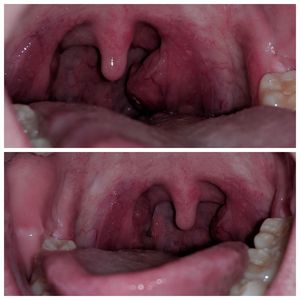

Patient had mono 2.5 years ago, tonsils swelled up and never went back to normal. Now one tonsil has been enlarged for 2 months. Patient is a social smoker. Throat constantly looks irritated. Has had a throat related sickness 4 times in the past 2 months. 9.1 x10E3/uL WBC. 5.22 x10E6/uL. Any ideas? Should they get a tonsillectomy